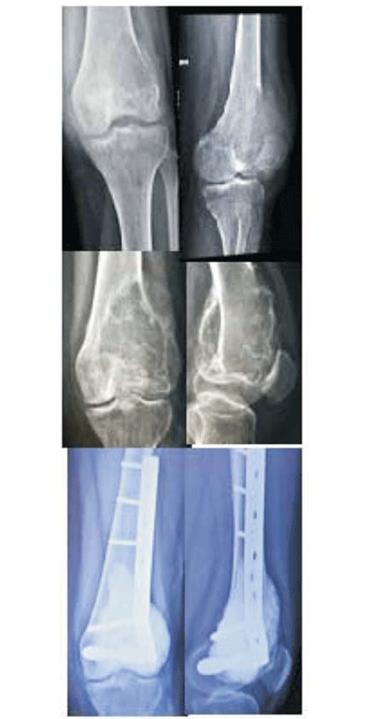

Paciente de 18 años, sexo femenino, sin antecedentes personales a destacar. Consulta en el año 2015 por gonalgia izquierda de tres meses de evolución, que agrega limitación en la marcha y tumoración de un tercio proximal de pierna. Se realiza estudio imagenológico con radiografía (Rx), tomografía computada (TC) y resonancia nuclear magnética (RNM) que evidencia lesión lítica de tibia proximal; la biopsia confirma el diagnóstico histopatológico de TOCG estadio III de Campanacci. En el momento del diagnóstico se plantea como tratamiento la no preservación de la epífisis tibial. Se decide iniciar tratamiento con denosumab 120 mg subcutáneo (con el objetivo de evitar sacrificar la epífisis), con un refuerzo de la misma los días 8 y 15 del primer mes. La dosis inicial se repitió mensualmente. Se realizaron controles clínicos y paraclínicos humorales e imagenológicos mensualmente. Al mes del control la paciente se presentaba sin dolor y con radiografías que ya hacían imposible el curetaje de la lesión. Se completaron seis meses de tratamiento con denosumab y se decidió discontinuar el mismo dado que la lesión se presentaba esclerosada, bien delimitada y con una paciente asintomática. (figura 1)

Abajo: después del tratamiento